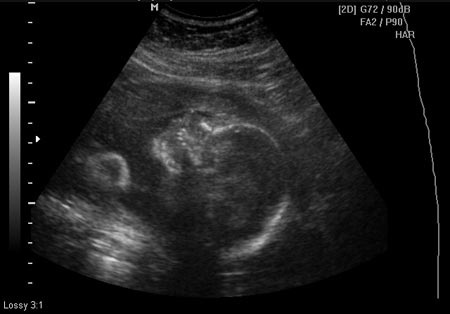

MiniMimi egész jól viselte a kukucskálást, amit kértem tőle, azt maximálisan próbálta teljesíteni, igazából nem lehetne panaszra okom, mutogatta, amit kellett, elég egyértelműen. Az egyetlen gond, amire nem is számítottam, hogy az arcát viszont takargatta a kezével, vagy belefúrta a fejét a méhlepénybe, így a pofijáról egy képet leszámítva nem sikerült jó képet csinálni. Talán még az is közrejátszott, hogy a mellső falon tapadt meg a méhlepény, így ez is nehezítette a nézelődést. Ettől függetlenül nagyon jó élmény volt, jó volt látni, ahogy mozog, forgolódik, dörzsölgeti a kis szemét.

A súlya már több mint fél kg és a hossza 27 cm, 4 cm-es hatalmas talpacskákkal. Érdekes volt látni, hogy a 2D-s képeken már látszottak a kis fogkezdemények az ínyében.

A nemét egyértelműen sikerült megmutatnia, nagyon ügyesen felhúzva tartotta a lábait, amíg alulról a doki bácsi megszemlélte. Az orvos kicsit érdekesen kezdte el felvezetni a nemét: közölte, hogy itt kellene lennie a herezacskónak, de olyan hangsúllyal mondta, mintha valami rendellenesség lenne. Aztán hozzátette, hogy itt pedig a hímvesszőnek, tehát, ha nincs ott egyik sem, akkor milyen nemű lesz - nézett ránk kérdőn… Ez itt egy kislány.